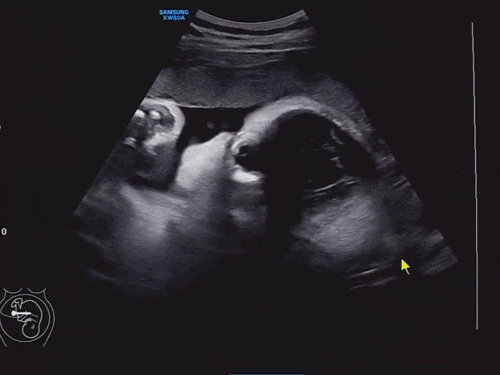

임신/출산) 33주차증상 초음파 제왕절개 날짜잡기

이제 30주차에 접어들면서 2주간격으로 병원진료를 보게되었어요. 주말엔 사람이 너무 많아서 왠만하면 혼...